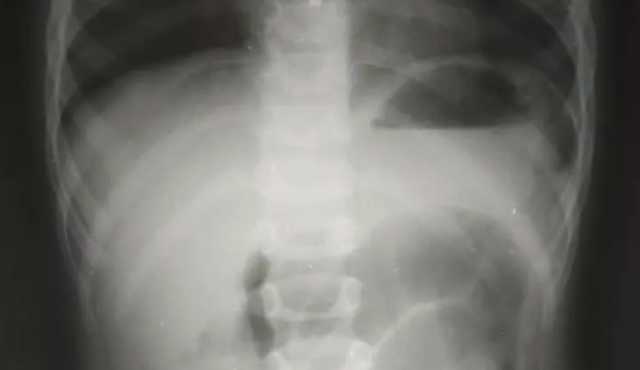

Дитячого хірурга Кирила Лапшина дуже здивував рентген-знімок. У черевній порожнині чітко візуалізувався дивний сторонній предмет, який за обрисами схожий на кулю від пневматичної гвинтівки.

Медик уточнив у тата хлопчика, чи міг син проковтнути кулю. Чоловік повідомив, що у них вдома є пневматична рушниця та до неї металеві кулі, якими дитина нещодавно гралася. Ймовірно, випадково хлопчик проковтнув одну з них. Все б закінчилося добре, якби куля потрапила зі шлунка в кишківник і вийшла.

Але в маленького пацієнта куля потрапила в апендикс, це стало причиною запального процесу, через що хлопчику знадобилася термінова операція.